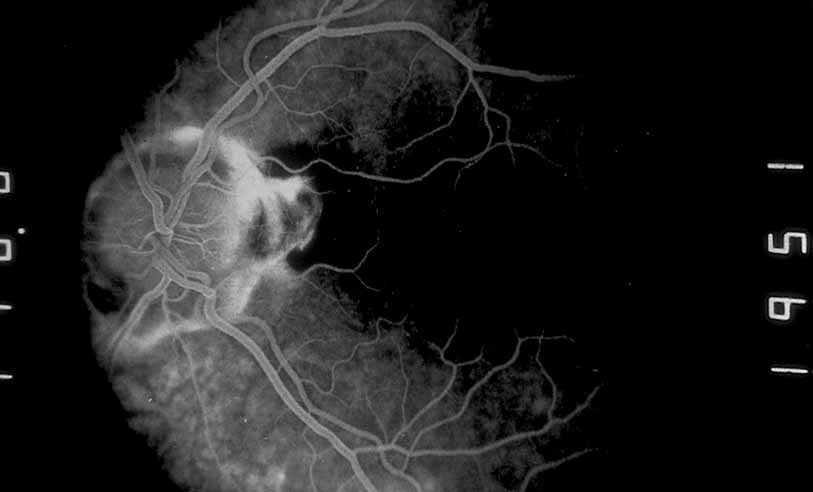

In addition to exudative detachment of the neurosensory retina and papillitis, patients with Vogt-Koyanagi-Harada disease as well as sympathetic ophthalmia may also develop serous detachment of the retinal pigment epithelium. This differs from the usual form of retinal pigment epithelium detachment that occurs in age-related macular degeneration by the absence of adjacent soft drusen and the presence of multiple pinpoint leak sites and disc staining characteristic of Vogt-Koyanagi-Harada disease (see Figs. 30, 31, 32, 33, and 34) and sympathetic ophthalmia (see Figs. 35 and 36).41–46 In cases of Vogt-Koyanagi-Harada disease with serous retinal detachment or detachment of the retinal pigment epithelium, some authors have reported hyperfluorescence of the large choroidal vessels in early stages of the angiogram, followed by dye leakage in the late phase of the study, whereas others report leakage from the choroidal vessels throughout the study (see Figs. 33 and 34).11,12

Fig. 31 Vogt-Koyanagi-Harada syndrome. Fluorescein angiography shows multiple spots of deep hyperflourescence within the serous detachment

Fig. 32 Vogt-Koyanagi-Harada syndrome. Later frames of the fluorescein show increased leakage with pooling.